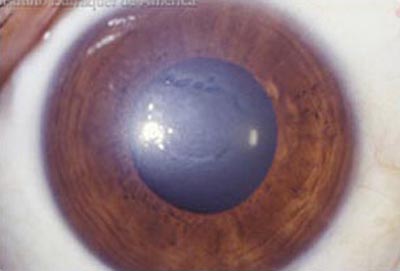

Descompensación de la Córneal Primaria

Distrofia Endotelial de Fuchs, conocida como córnea Guttata por el aspecto de las verrugosidades que aparecen en el endotelio. Con retroiluminación, (reflejo rojo) el aspecto endotelial es el de la plata martillada. Es una entidad familiar hereditaria y progresiva pero que toma décadas para desarrollarse. Produce pérdida de la transparencia de la córnea por incapacidad del Endotelio para mantener el estado de deshidratación corneal.

Los signos y los síntomas de la distrofia se hacen evidentes después de los 50 años con visión borrosa mayor al despertarce que mejora a lo largo del día. A medida que progresa, los periodos de emborronamiento se van haciendo más largos y permanentes.

Descompenzación Corneal

Descompenzación Corneal